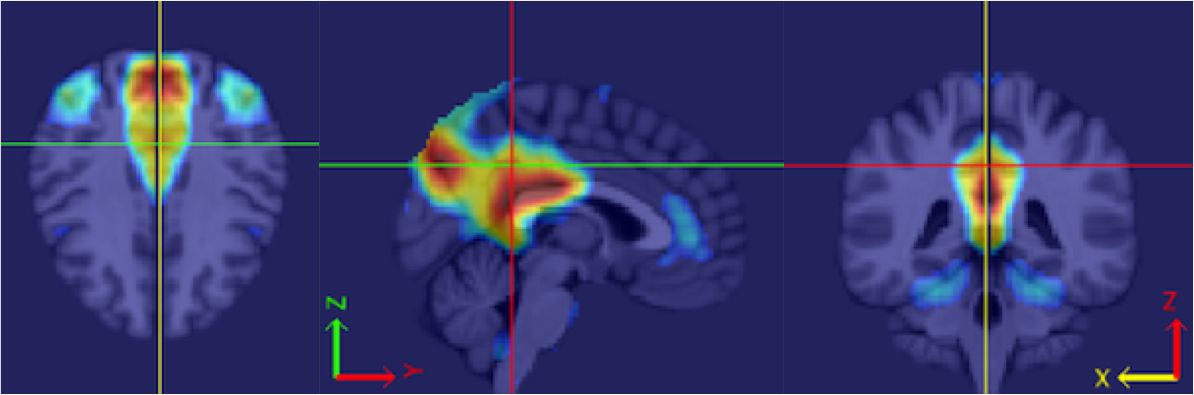

Our procedure is as follows. Each fMRI scan was separated into left and right hemispheres. Thus, each hemisphere contained voxels. Similar to standard group ICA (Calhoun et al., 2001b), a dimension reduction using PCA was applied to each hemisphere of each subject. 15 PCs are obtained for each hemisphere. A group data matrix was generated by concatenating the reduced data of both hemispheres of the 20 subjects in the temporal domain. Thus, the aggregated matrix has dimension , where , , and . Our algorithm of homotopic group ICA is then applied on this matrix. Fifteen estimated independent components are postulated by H-gICA. As shown in Figure 12, out of the 15 components, several brain networks were found including: the visual network 12, the default mode network 12, the auditory network 12, and the motor network 12. Compared with the ICs obtained from ordinary gICA, shown in 12, 12, 12 and 12, H-gICA improves the estimation of all of these sources by yielding substantially more clearly delineated networks.